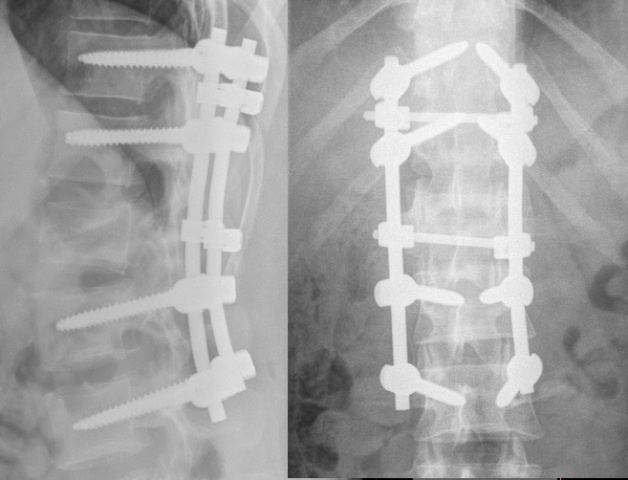

Пострадавшему уже провели операцию и зафиксировали позвонки с помощью специальных винтов. Однако на этом лечение не заканчивается, мужнину ждет еще одно хирургическое вмешательство, чтобы стабилизировать позвоночник. А дальше — долгое восстановление.

Фото: министерство здравоохранения Красноярского края